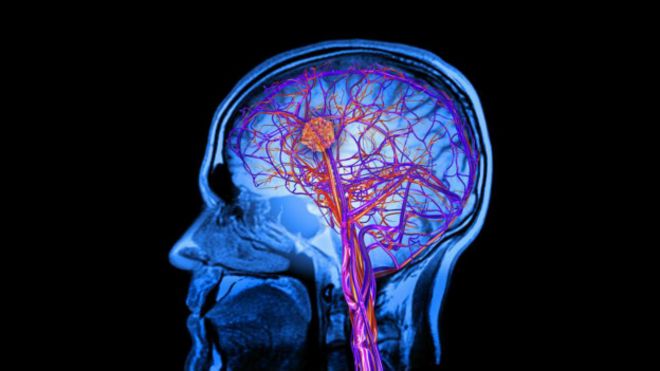

Beyindeki herhangi bir hasar nedeniyle bilincinizi yitirmişseniz komadasınız demektir. Bunu herkes bilir. Ama bazen komaya yakın durumlar vardır. Hastanın gözleri açıktır ama hiçbir bilinç belirtisi yoktur. Bitkisel hayat ya da ‘tepkisiz uyanıklık sendromu’nda hasta uyanık görünür, hatta bazen uykuya dalar, ama dış dünyaya hiçbir tepki vermez. Arada bir isimlerinin söylenmesine ya da gözleriyle bir ışık kaynağını takip etme şeklinde tepki gösteren hastalar ise ‘asgari bilinç hali’ olarak tanımlanır. Bu iki kategorideki hastalar, bilinçli hareket etme ya da dış dünyaya düzenli tepki verme belirtisi göstermez. Yakın zamana kadar bu hastaların içlerinde yaşadıkları bilinçlilik düzeyi konusunda kimse bir şey bilmiyordu.

Image copyrightGettyBilişsel nörolog Adrian Owen öncülüğünde son on yıldır yapılan araştırmalar, bilinçle ilgili bu gri alanlara ilişkin düşüncemizi değiştirdi. Beyin taramaları sonucu elde edilen veriler, ‘uyanık koma’ halindeki hastaların beşte birinin bilinçli olduğunu gösteriyor. Bu hastalardan tenis oynadıklarını hayal etmeleri istendiğinde, beyinlerindeki hareket kontrolü ile ilgili bölgenin aktif hale geldiği, evlerindeki bir odaya girdiklerini düşünmeleri istendiğinde beyinlerindeki navigasyon bölgesinin aktifleştiği görüldü. Bu sinyalleri kullanma yoluyla az sayıdaki bazı hastalar dış dünya ile iletişime bile geçebilmiş, gözlemciler onların sorulara verdiği cevapları beyin taramasında tahmin edebilmişti.

Filmin her iki versiyonu izlenirken çekilen beyin taramaları karşılaştırıldığında, gerilim içeren orijinalde korteksin neredeyse tamamının aktif olduğu görülüyordu: Duyusal bölgeler, motor bölgeleri, hafıza ve beklenti ile ilgili bölgelerin tümü aktifti. Beynin planlama, beklenti, bilgi harmanlamadan sorumlu ‘idari’ kısımlarının filmdeki gerilim anlarıyla eşzamanlı şekilde yükselip alçalması önem taşıyordu. Bu, olayın gelişimini anladığınızı gösteriyordu.

Image copyrightGettyNaci daha sonra filimi ‘uyanık koma’ halindeki iki hastaya izletti. Birinde sadece işitme korteksi aktif hale gelmişti. Yani bu hastanın beyni belki de sadece otomatik olarak sese karşı tepki veriyordu. Fakat 16 yıldır hiçbir tepki vermeyen ikinci hastanın beyninde aktif hale gelen alanlar sağlıklı deneklerinkiyle aynıydı. Korteksteki aktivite filmin akışına göre yükselip alçalıyor, filmdeki gelişmeleri anladığına işaret ediyordu.